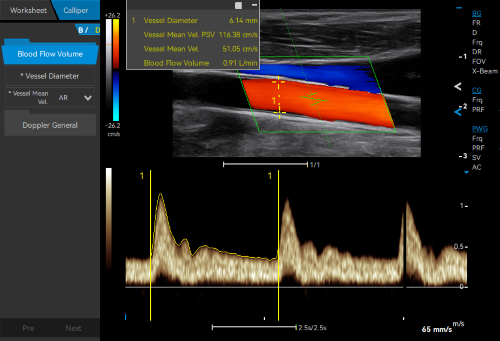

- Category: Color Doppler